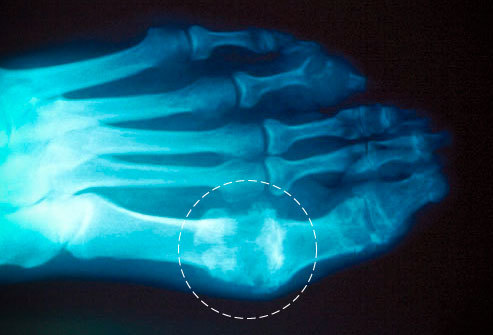

其实 , 这种对痛风的认识是非常表面的 , 甚至有点“天真”了 , 有这种想法的人对痛风严重的后果知之甚少 。 疼痛仅仅是发作初期的一种表现 。 据统计 , 90%以上的痛风首次发作是在第一跖趾关节 , 也就是大拇指与足部连接的第一个关节 。 除了疼痛以外 , 还会有肿胀、发红、发热的表现 , 一次发作可能会痛到不能穿鞋、走路 , 甚至不能工作 。 如果不加干预 , 进一步发展会在关节局部形成痛风石 , 累及更多的关节 , 最终导致手、足等部位的关节变形 , 致残 。 痛风石有两种表现:一种是逐渐向皮肤突破 , 最终从破溃的皮肤表面溢出 , 并继发感染 , 最终截肢;另一种是向内 , 向关节里面走 , 逐渐侵蚀骨质 , 将正常的骨质结构破坏掉 , 从X片上看 , 这种被侵蚀的部位会显出骨头缺损 。